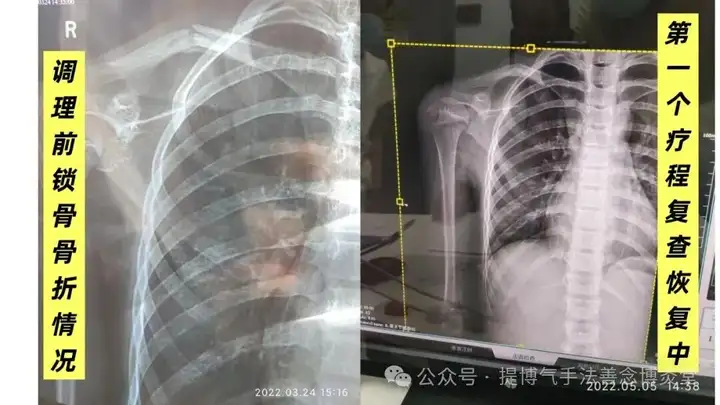

2022年三月,患者女,12岁左右。右侧锁骨骨折。

因摔跤运动导致左侧锁骨骨折。

调理时间:2个疗程

这个患者之所以持续了2个疗程的调理,是因为孩子要上学,第一个疗程我们是每天去学校给予调理,她还要活动,断位没有固定。后来第一个疗程结束时,我们发现骨折恢复的不好,就立马咨询恩师马源泽老师,恩师告知在未完全康复前需要静养+固定。后来我们建议家属把孩子接出学校,来调理馆安心调理。第二个疗程实际只调理了7天,孩子以卧床静养为主。休息了7天后返回学校,半个月复查一次,复查第二次时已完全康复。